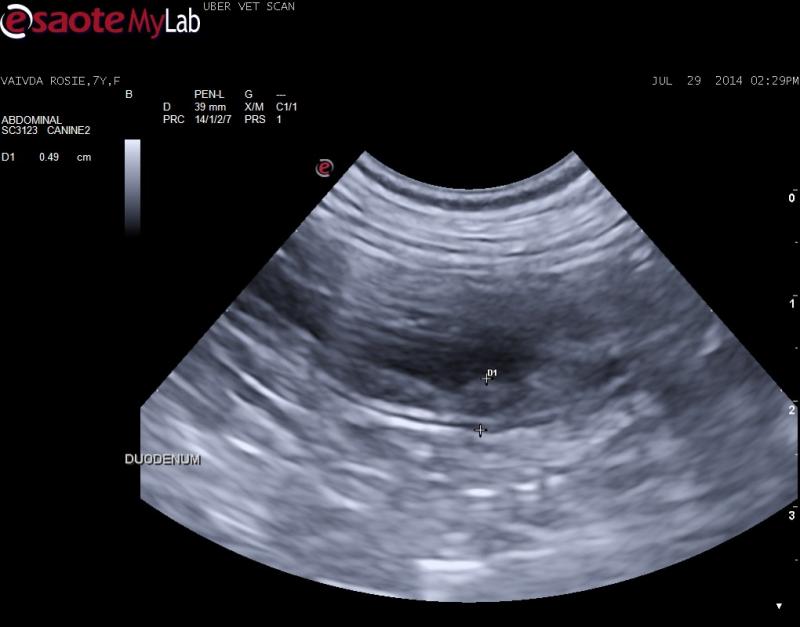

– mucosal layer of duodenum and upper GI appears thick and hyperechoic – possible luminal mass with loss of normal layering

– mucosal layer of duodenum and upper GI appears thick and hyperechoic – possible luminal mass with loss of normal layering

Nice image set Jacquie, for most of the bowel the lesions are mucosal but for about 2 cm the lesion goes transmural but the serosa is minimally affected. I would cut it out as carcinoma does this and the key tis to get carcinoma out early. However intraoperative ultrasound is key here to 1) find the lesion since no serosal changes for the surgeon to see easily because at the moment th epathology is mural and luminal and 2) to delineate solid healthy layered intestine to R&A. Other things that do this are focal ibd/granulomatous, spontaneous necrosis and focal complicated enteritis… maybe lsa but doubt it. Also be sure its there right before sx so it doesn’t “heal itself” before your go in.

Nice image set Jacquie, for most of the bowel the lesions are mucosal but for about 2 cm the lesion goes transmural but the serosa is minimally affected. I would cut it out as carcinoma does this and the key tis to get carcinoma out early. However intraoperative ultrasound is key here to 1) find the lesion since no serosal changes for the surgeon to see easily because at the moment th epathology is mural and luminal and 2) to delineate solid healthy layered intestine to R&A. Other things that do this are focal ibd/granulomatous, spontaneous necrosis and focal complicated enteritis… maybe lsa but doubt it. Also be sure its there right before sx so it doesn’t “heal itself” before your go in.